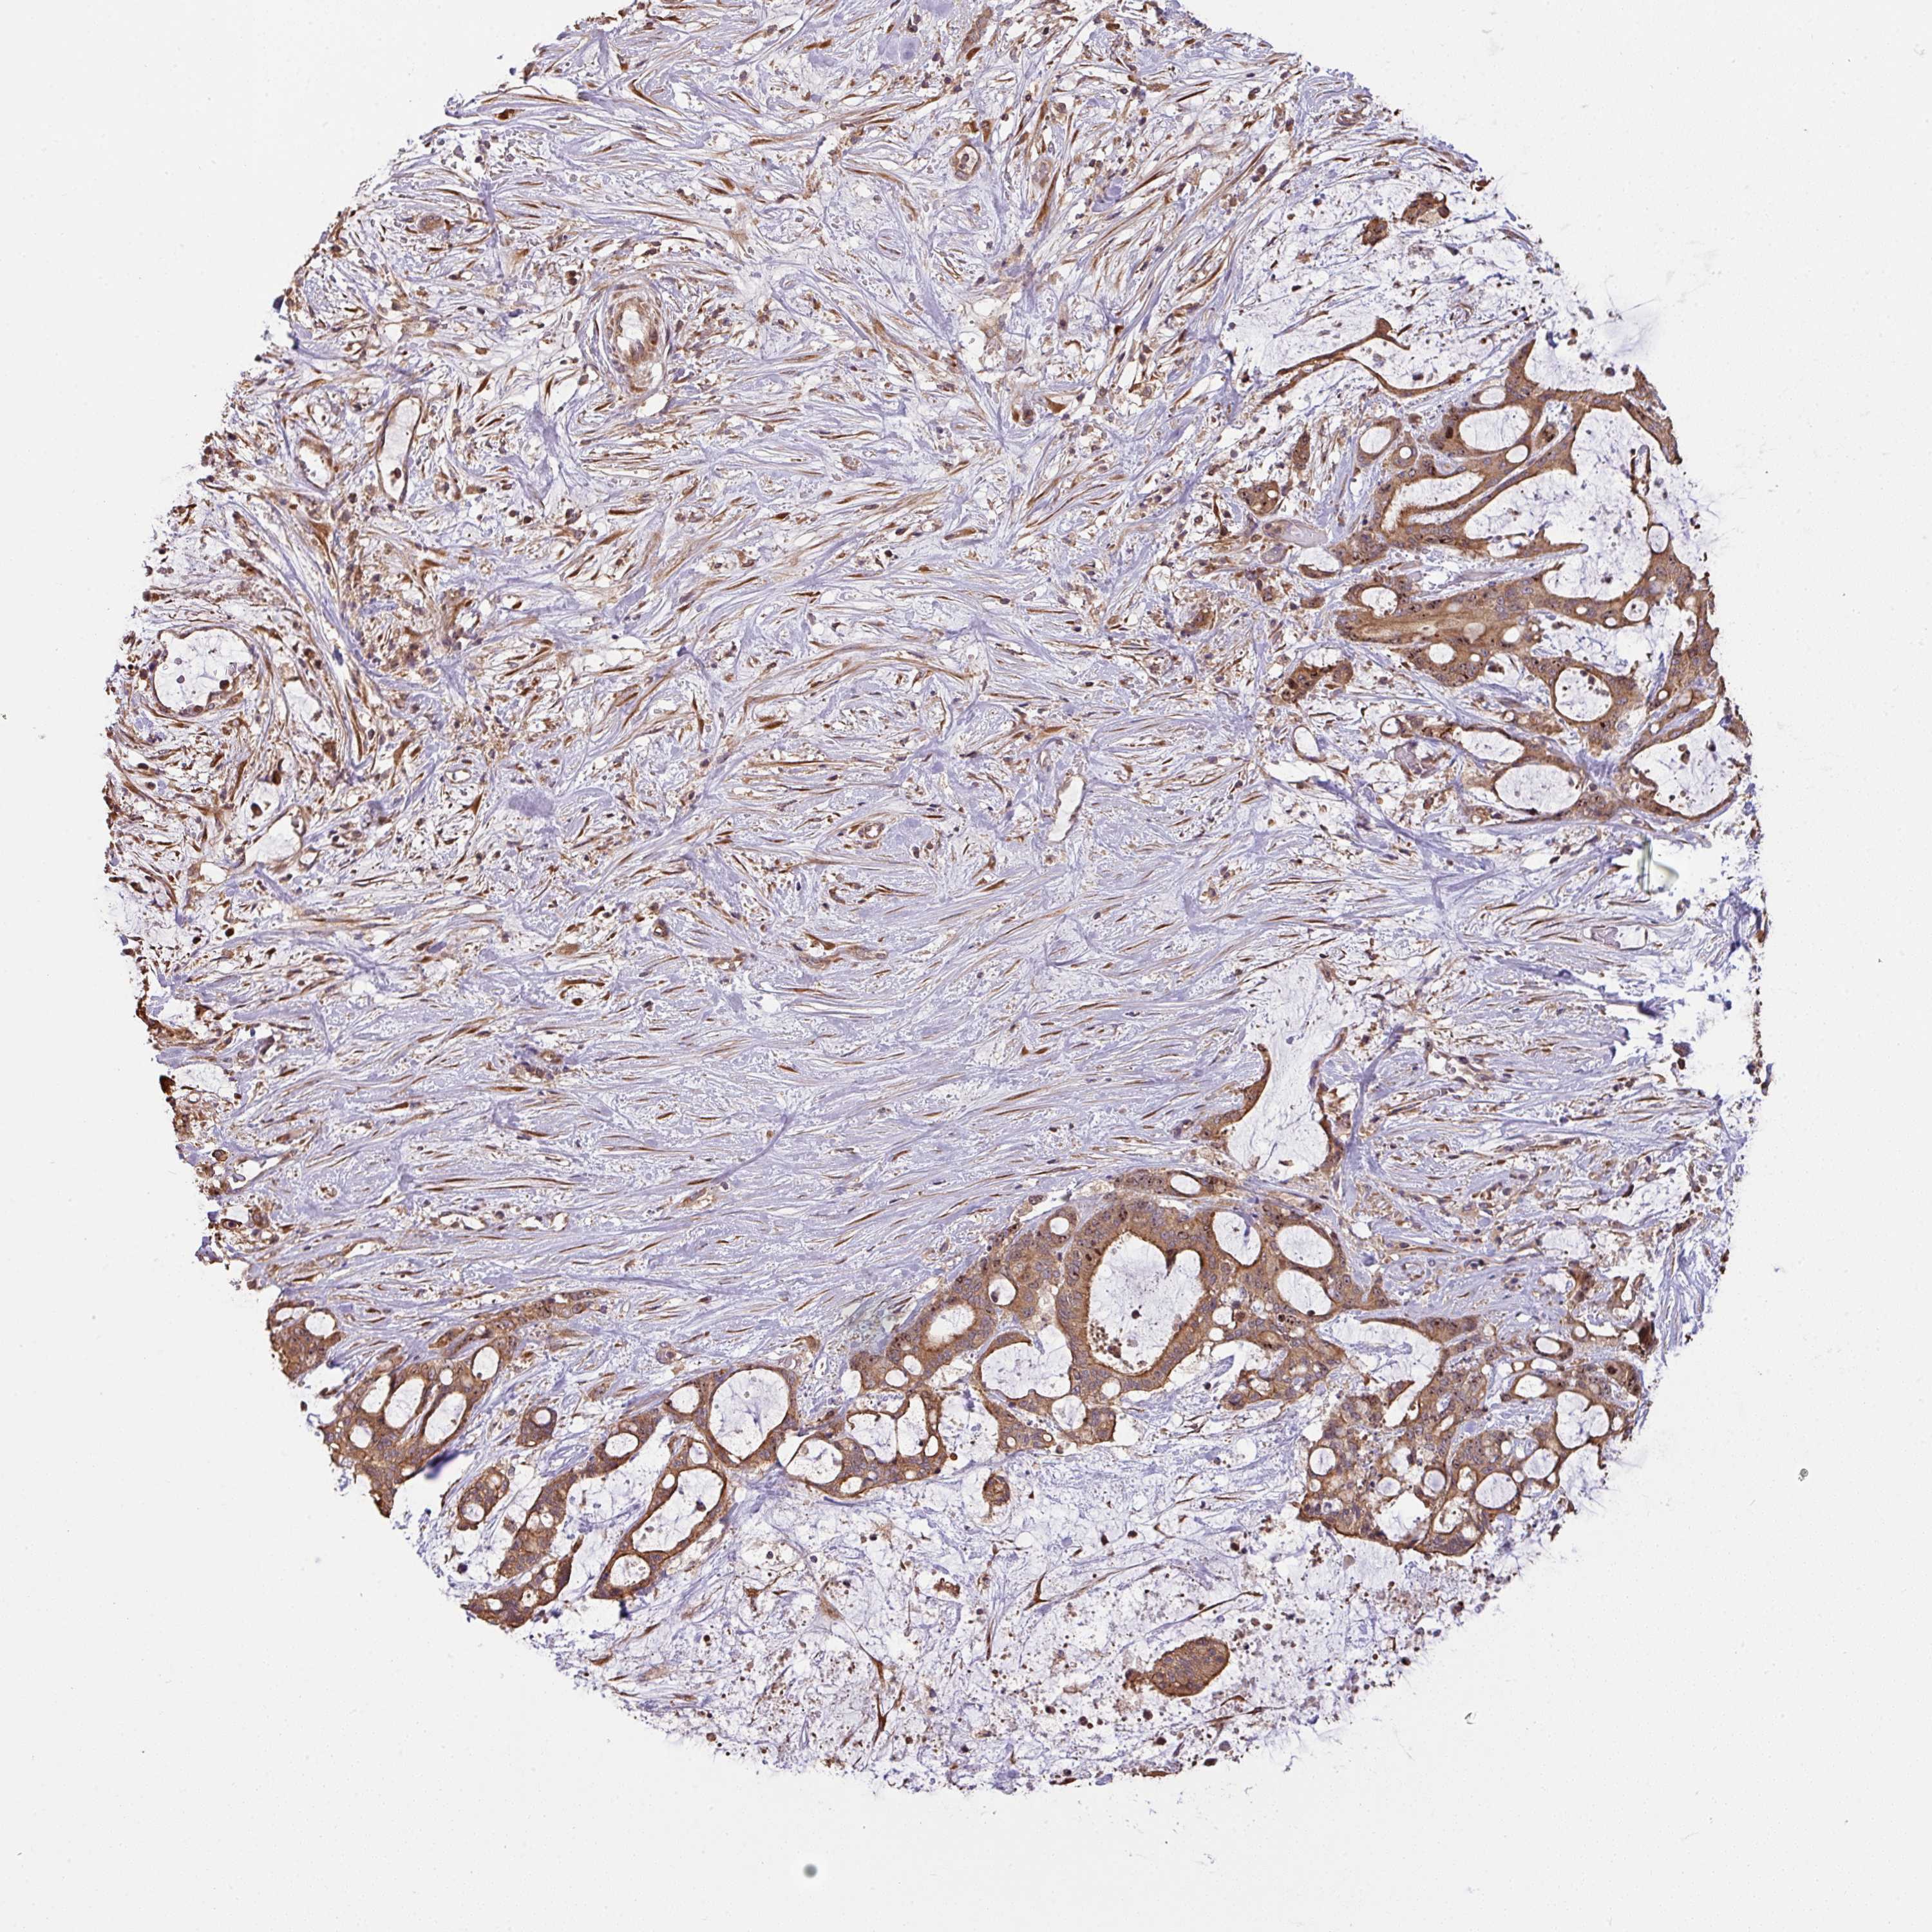

LIVER CANCER - Protein expressioni

A mouse-over function shows sample information and annotation data. Click on an image to view it in a full screen mode. Samples can be filtered based on level of antibody staining by selecting one or several of the following categories: high, medium, low and not detected. The assay and annotation is described here.

Note that samples used for immunohistochemistry by the Human Protein Atlas do not correspond to samples in the TCGA dataset.

Antibody stainingi

Antibody staining in the annotated cell types in the current human tissue is reported as not detected, low, medium, or high, based on conventional immunohistochemistry profiling in selected tissues. This score is based on the combination of the staining intensity and fraction of stained cells.

Each image is clickable and will lead to virtual microscopy that enables deeper exploration of all samples and also displays staining intensity scores, fraction scores and subcellular localization as well as patient and tissue information for each sample.

Antibody HPA050955

Staining

High

Medium

Low

Not detected

Intensity

Strong

Moderate

Weak

Negative

Quantity

>75%

75%-25%

<25%

None

Location

Nuclear

Cytoplasmic/membranous

Cytoplasmic/membranous,nuclear

Cholangiocarcinoma

Carcinoma, Hepatocellular, NOS